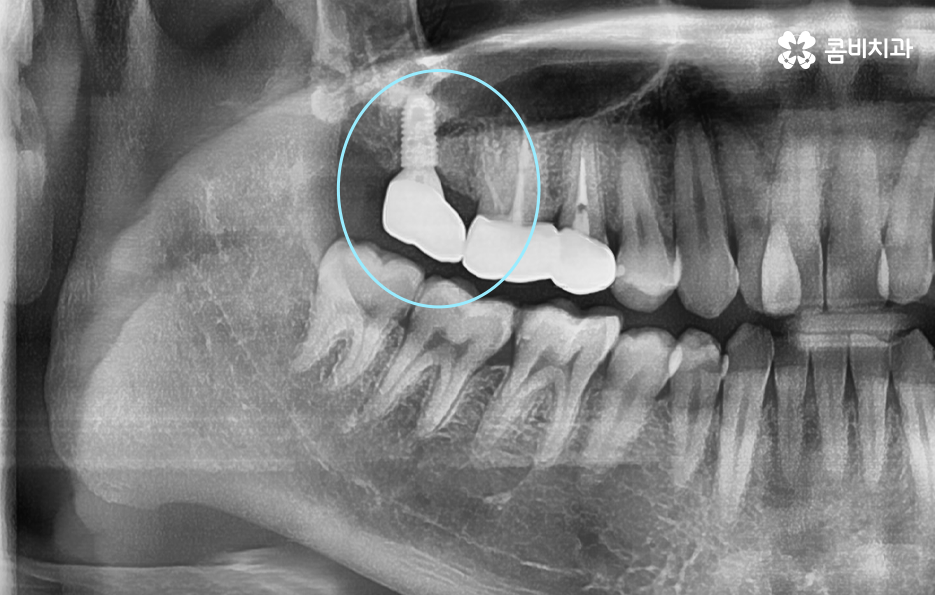

오늘은 자연치아를 결국 잃게 되면 대표적인 사례 중에서 오래된 보철물 혹은 보철물 관리가 잘 안되어 결국 발치로 이어지는 사례에 대해서 알아볼 거예요. 오래된 보철물 속에서 진행되는 2차 충치는 알아차리기도 쉽지 않고 이미 깊어지면 치아 뿌리 쪽으로 충치가 진행되어 발치로 이어지는 경우가 많다는 점에서 보철물 관리의 중요성에 대해서 재인식하는 포스팅이 되길 바라고 있어요

보통 어금니 크라운을 씌운 경우에는 신경치료를 한 후에 크라운을 씌운 경우가 많기 때문에 이미 크라운 속에 충치가 심하게 진행되어도 통증과 같은 증상으로 문제를 잘 못느끼는 경우가 많이 있는데요

치아 문제에 대해서 안아프면 별 문제 없겠지 하고 잘 지내고 있다가 예전에 씌워서 기억도 잘 안나는 크라운이 흔들리거나 냄새, 잇몸 염증 등이 발생하여 치과를 찾게 되었는데 이미 심각한 수준으로 치아 내부에 충치가 진행되어 결국 발치에 이르게 되는 경우가 많이 있어요

크라운 혹은 오래된 보철물 내부에 2차 충치가 발생된 경우에 자연치아를 보존할 수 있는지에 대한 판단은 엑스레이 만으로 진단할 수 있는 문제는 아니며 치아 내부에 충치가 어느정도나 진행되었고 잔존하는 치아의 양이 어느정도나 되는지에 따라서 발치 혹은 치아 보존 치료에 대한 판단을 할 수 있어요

이미 신경치료를 했던 치아라고 해도 보철물 제거 후에 충치를 잘 치료하고 재신경치료를 통해서 치아를 보존할 수 있는 경우가 있고 발치 후 임플란트를 해야하는 경우도 있는데요

이러한 판단 기준은 치아 내부에서 충치가 발생되었을 때 충치가 얼마나 치아 뿌리 쪽으로 깊어졌는지 혹은 살릴 수 있는 치아가 얼마나 잔존하는지에 따라서 다르며 치과의사 역시도 치아 속을 확인해보고 충치를 제거해봐야 알기 때문에 치과의사의 숙련도, 경험도 중요하겠지만 치과의 내원 시점이 무척이나 중요하기 때문에 보철물이 오래된 경우에는 꼭 주기적으로 치과 검진을 하시고 의사의 소견 하에 크라운의 교체가 필요하다면 문제가 커지기 전에 재치료를 적절히 받는 것이 자연치아 보존에 중요할 거예요